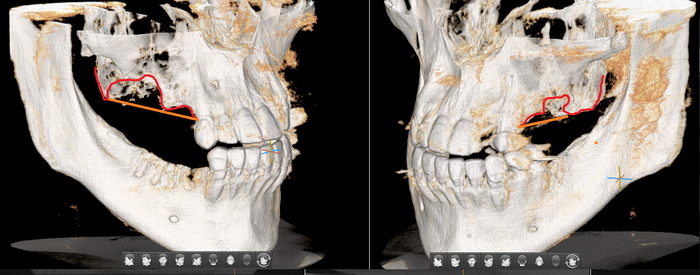

Фрагмент компьютерной томографии (вид сбоку):

Первый вопрос, который я задал, – почему не было проведено исправление прикуса до имплантации?